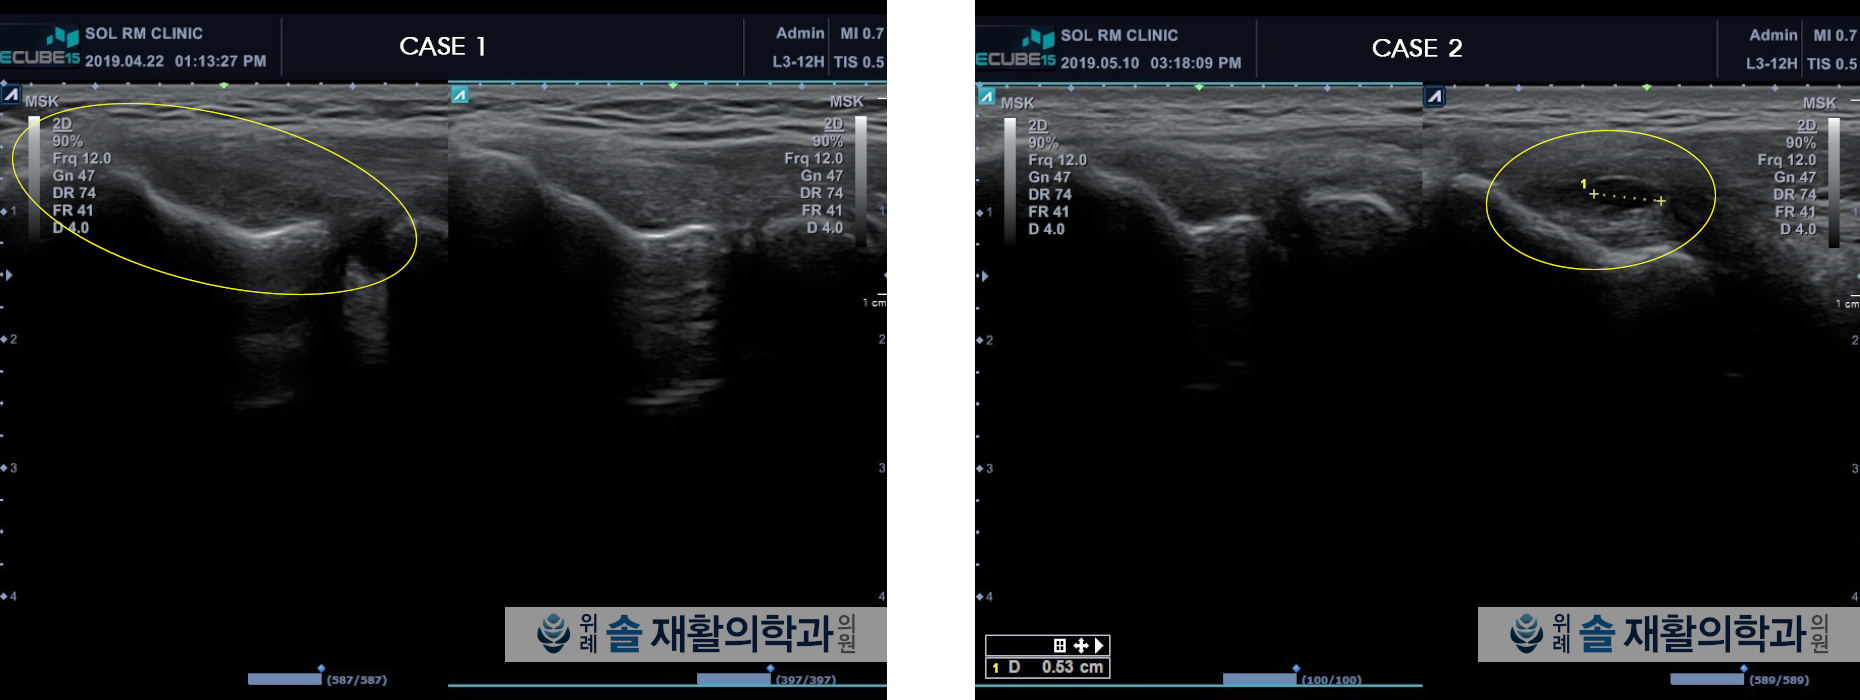

테니스 엘보우와 골프 엘보우의 정확한 진단명은 외측 상과염내측 상과염 입니다. 위팔뼈의 팔꿈치 측 바깥쪽과 안쪽을 만지면 뼈가 도드라져 있는 부위가 외측 상과와 내측 상과 부위이며, 이 부위에 통증이 생기는 질환이라고 볼 수 있습니다. 사실 진단명이 외/내측 상과염으로 되어있어서 염증성 질환으로 생각할 수 있겠지만, 엄밀히 따져서는 염증보다는 대표적인 힘줄의 과사용 손상(Overuse injury)으로 보고 있습니다. 팔꿈치 외/내측 상과에서 시작하여 손까지 이어지는 전완부의 근육을 많이 사용함에 따라서, 손목 편금과 굽힘근의 시작점인 팔꿈치 부위의 힘줄에 퇴행성 변화가 일어나는 것입니다.

외/내측 상과염은 예전에는 염증성 질환으로 생각하고 소염제 복용, 염증주사(스테로이드)를 통해 염증 감소 목적으로 하는 치료를 시행하였는데, 즉각적인 치료효과는 좋았지만 시간이 지나면 100% 재발률을 보여서 치료에 꽤 애를 먹었던 질환입니다. 이유는 치료 방향의 접근이 잘못되었던 탓입니다. 힘줄의 과사용으로 퇴행성 변화로 약해진 힘줄이 원인이기 때문에 염증만 가라앉혔더라도, 시간 지나서 손을 많이 사용하면 다시 무리가 가면서 통증이 발생하기 때문입니다.